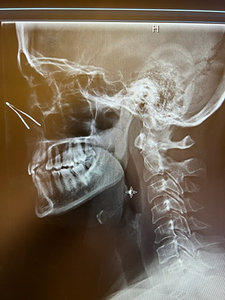

While the case was unremarkable clinically, it provided an interesting radiological feature. An artifact was present on the lateral radiograph. The artifact was not visible on the AP or APOM radiographs, as positioning for those images is lower, more caudal, than for the lateral view.

The artifact was the metal in the nose area of the N-95 mask the patient wore during the radiographic procedure (See X-ray) – a "sign of the times."